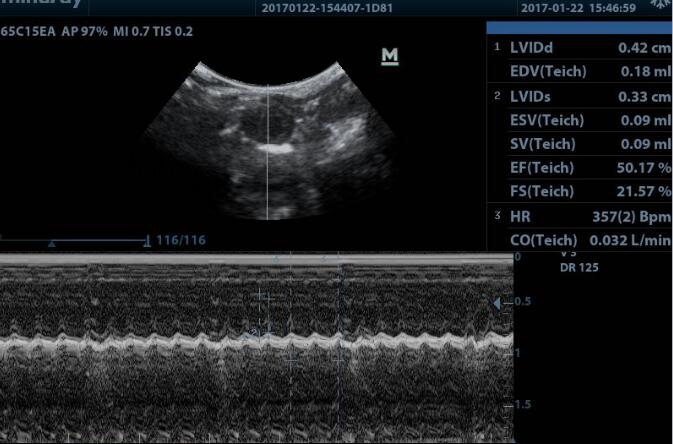

1.由Laplace定理可知 :S=Pr/2h,P为心室内压,r为心腔内径,h为心壁厚度。在心脏压力负荷过重的情况下,为适应心脏做功增加,室壁厚度增加,左室室壁应力增加,提高心脏收缩功 能起到早期代偿的机制 ;但持续的压力超负荷,可促进心肌肥厚,导致心肌细胞的坏死及凋亡,心脏的收缩和/或舒张功能受到损害,最终发展为慢性心力衰竭甚或心源性猝死。可通过超声或血流动力学检测来评价心功能。M超图像,测量左室舒张末期及收缩末期内径(LVIDd、LVIDs),同时系统将会自动计算出相应的射血分数(EF%)及左室短轴缩短率(FS%)。